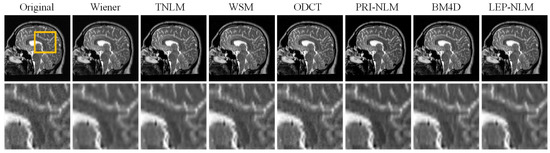

3.2. Real MR Images